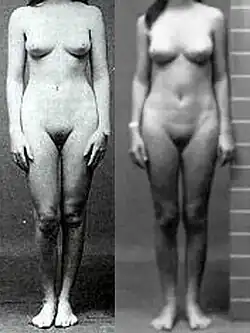

Complete androgen insensitivity syndrome (CAIS) is an AIS condition that results in the complete inability of the cell to respond to androgens.[1][2][3] As such, the insensitivity to androgens is only clinically significant when it occurs in individuals who are exposed to significant amounts of testosterone at some point in their lives.[1] The unresponsiveness of the cell to the presence of androgenic hormones prevents the masculinization of male genitalia in the developing fetus, as well as the development of male secondary sexual characteristics at puberty, but does allow, without significant impairment, female genital and sexual development[3][4] in those with the condition.

XY individuals affected by CAIS develop a normal external female habitus, despite the presence of a Y chromosome,[1][5][6][7][8][9] but internally, they will lack a uterus, and the vaginal cavity will be shallow, while the gonads, which differentiated into testes in the earlier separate process also triggered by their Y chromosome, will remain undescended in the place. This results not only in infertility in individuals with CAIS, but also presents a risk of gonadal cancer later on in life.[10]

Individuals with complete androgen insensitivity syndrome (grades 6 and 7 on the Quigley scale) are born with an external female phenotype, without any signs of genital masculinization, despite having a 46,XY karyotype.[18] CAIS is usually recognized at puberty,[2] which may be slightly delayed,[19] but is otherwise normal except for absent menses and diminished or absent secondary terminal hair.[1] Axillary hair (i.e. armpit hair) fails to develop in one third of all cases.[20] The vulva is normal, although the labia and clitoris are sometimes underdeveloped.[21][22] Vaginal depth varies widely for CAIS, but is typically shorter than normal;[1] one study of eight people with CAIS measured the average vaginal depth to be 5.9 cm [23] (vs. 11.1 ± 1.0 cm for unaffected women [24]). In some extreme cases, the vagina has been reported to be aplastic (resembling a "dimple"), though the exact incidence of this is unknown.[25]

Other subtle differences that have been reported include slightly longer limbs and larger hands and feet due to a proportionally greater stature than unaffected women,[40][41][42] larger teeth,[43][44] minimal or no acne,[45] well developed breasts,[46] a greater incidence of meibomian gland dysfunction (i.e. dry eye syndromes and light sensitivity),[47] and dry skin and hair resulting from a lack of sebum production.[48]